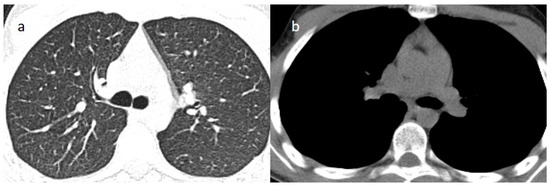

2. Case Presentations

- Brogna, B.; Bignardi, E.; Salvatore, P.; Alberigo, M.; Brogna, C.; Megliola, A.; Musto, L. Unusual presentations of COVID-19 pneumonia on CT scans with spontaneous pneumomediastinum and loculated pneumothorax: A report of two cases and a review of the literature. Heart Lung 2020, 49, 864–868. [Google Scholar] [CrossRef]